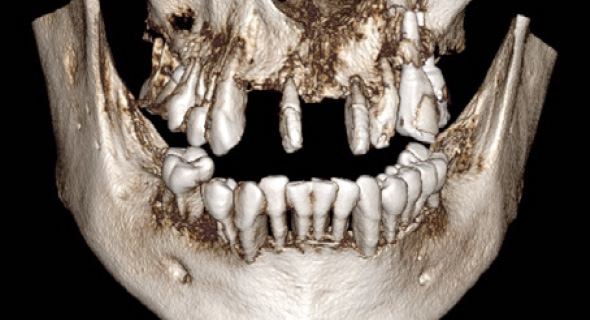

STEP 01

CT 촬영 및 진단

- 3차원 CT 촬영

- 뼈, 신경 분석 및 진단 -

01

100% 3D CT 촬영하여,

뼛속 신경까지 정확하게 진단 후 수술합니다. -